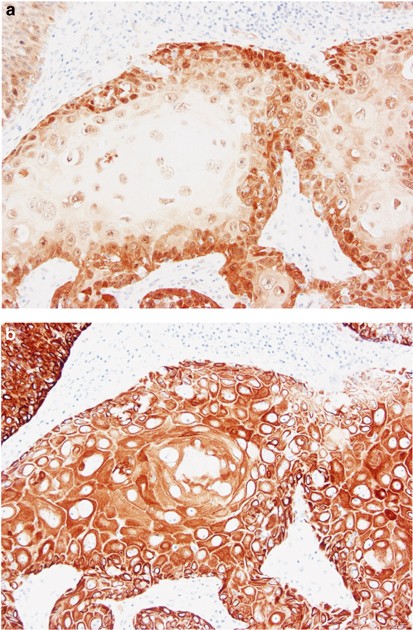

p16INK4a protein expression was evaluated by immunohistochemistry in 35 skin lesions of which 10 were actinic keratoses, 12 squamous cell carcinomas in situ and 13 invasive squamous cell carcinomas. All lesions were p16INK4a positive with highly variable staining intensities and fraction of positive tumor cells. The subcellular localization of the p16INK4a staining varied considerably and was therefore also delineated (Table 1). Actinic keratosis had in general rather weak p16INK4a staining and the staining was mainly cytoplasmic with occasional positive nuclei in some lesions (Figure 1a and b). Out of 12 squamous cell carcinomas in situ, 11 showed a strong nuclear and cytoplasmic p16INK4a staining (Figure 1c and d), which was in sharp contrast to surrounding normal keratinocytes. The remaining squamous cell carcinoma in situ also had a strong p16INK4a staining although with a mixed pattern of areas with cytoplasmic staining and areas with both nuclear and cytoplasmic staining. Of the invasive squamous cell carcinomas, nine had only cytoplasmic p16INK4a staining (Figure 1e and f) and four combined nuclear and cytoplasmic staining (Figure 1g and h) (Table 2). The intensity of the p16INK4a staining in invasive squamous cell carcinomas varied from weak staining in some tumors to very strong staining in others. To further validate the p16INK4a staining, Western blotting was performed using protein extracts prepared from frozen actinic keratoses, squamous cell carcinomas in situ and invasive squamous cell carcinomas with available p16INK4a immunohistochemistry data. The Western blot produced a 16 kDa band with varying intensities corresponding to p16INK4a in all tested tumors (Figure 2) confirming the immunohistochemistry data.

p16INK4a staining in precancerous and cancerous forms of squamous cell carcinoma of the skin. Actinic keratosis with cytoplasmic staining (a, b), p16INK4a staining in squamous cell carcinoma in situ showing full-thickness staining (c, d), invasive squamous cell carcinoma with cytoplasmic staining only (e, f) and both nuclear and cytoplasmic staining (g, h).